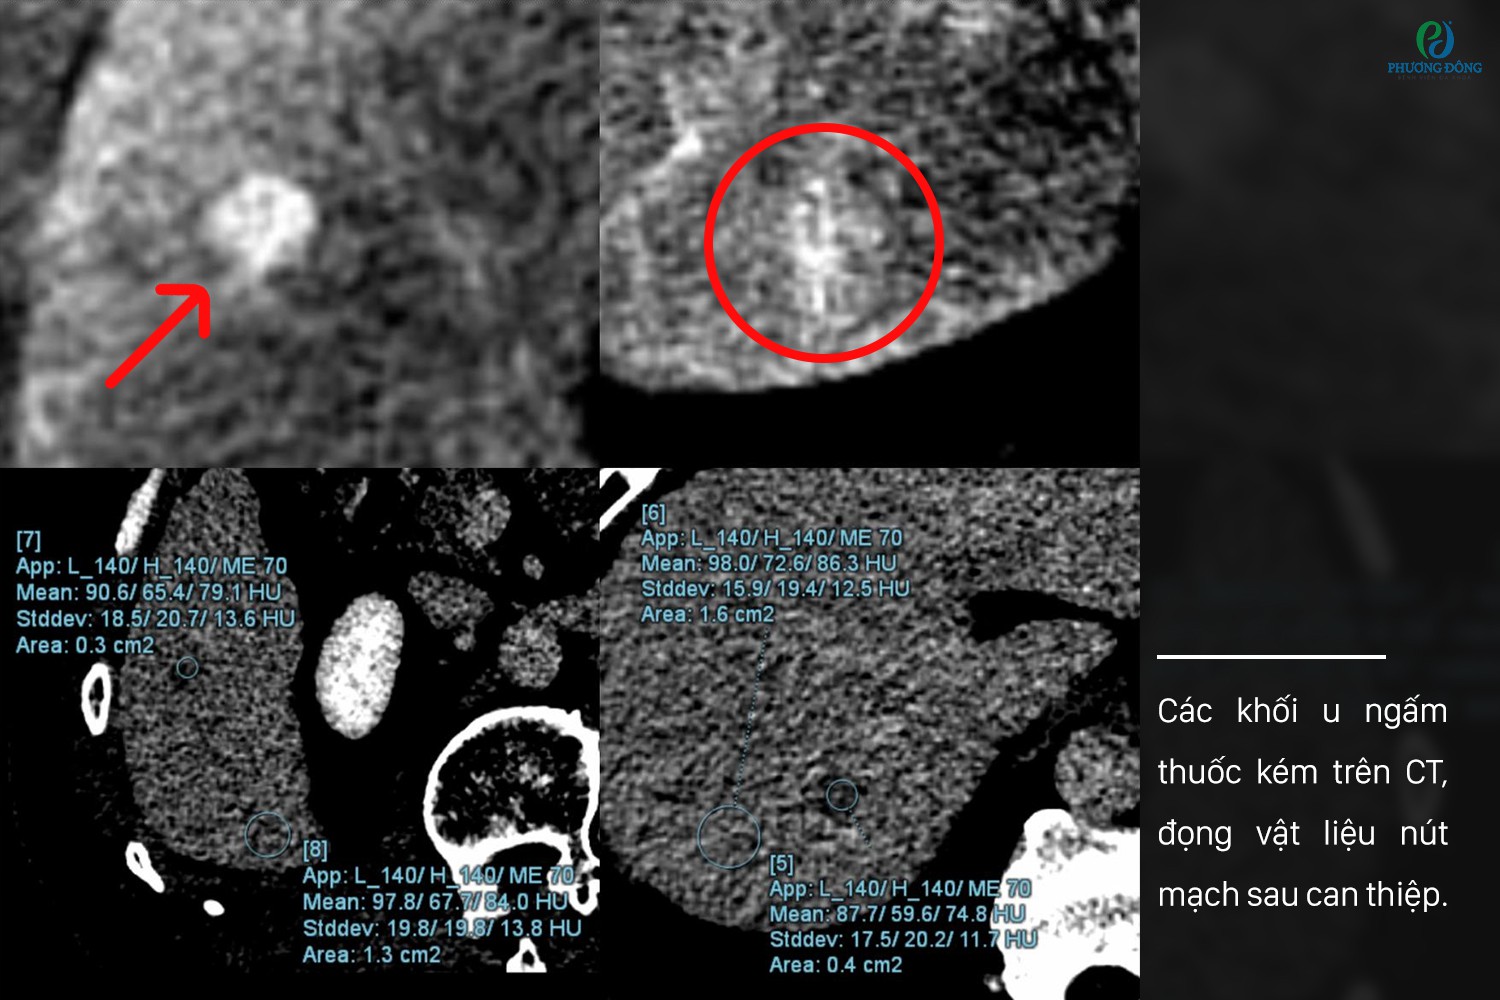

Tại Bệnh viện Đa khoa Phương Đông, bệnh nhân được thăm khám bằng hệ thống CT Photon Naeotom Alpha - nền tảng chẩn đoán hình ảnh tiên tiến, hỗ trợ đánh giá tổn thương chuyên sâu trong những trường hợp phức tạp. Kết quả từ CT Photon cho thấy hai khối u nhỏ sau thời gian điều trị gần như đồng tỷ trọng với nhu mô gan ở thì không tiêm, và sau tiêm ngấm thuốc kém hơn nhu mô gan ở các thì động mạch và tĩnh mạch cửa, gây khó khăn cho việc đánh giá bản chất tổn thương bằng hình ảnh thông thường.

Các khối u ngấm thuốc kém trên CT, đọng vật liệu nút mạch sau can thiệp

Tuy nhiên, thách thức tiếp tục xuất hiện trong phòng can thiệp. Trên chụp mạch số hóa xóa nền (DSA), các tổn thương tăng sinh mạch kém, rất khó nhận biết rõ ràng. Để giải quyết vấn đề này, ê-kíp đã sử dụng Cone-beam CT kết hợp kỹ thuật siêu chọn lọc nhằm xác định chính xác vị trí tổn thương và vùng cấp máu theo phân thùy gan. Kết quả cho thấy các khối u đọng vật liệu nút mạch tốt, phù hợp với mục tiêu điều trị đặt ra.